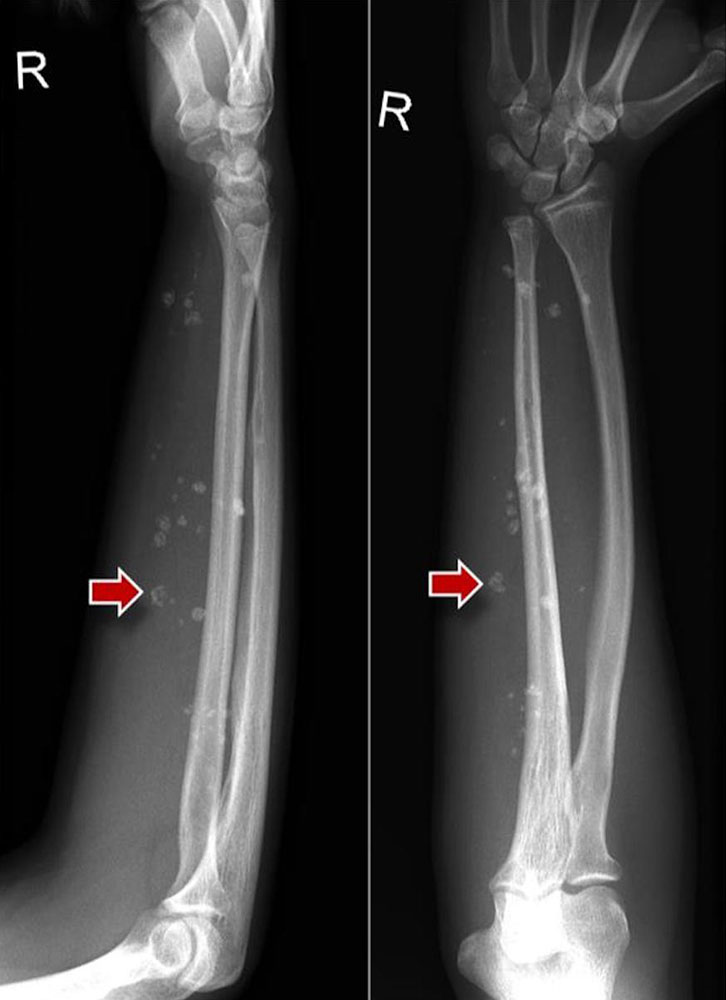

Occasionally phleboliths are visible on conventional images in patients with venous malformation.

Phleboliths are pathognomonic for the presence of a venous malformation outside the pelvis. In patients with arteriovenous malformation, the cortex of an affected bone may be thickened or lytic. Not infrequently, tubular defects are also recognizable in intraosseous AVMs.